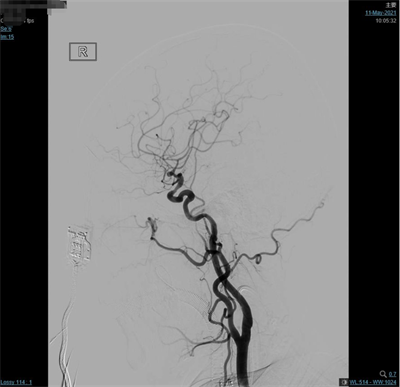

夹闭前造影

患者气管插管全麻满意后,双侧腹股沟区常规消毒铺巾,右侧腹股沟韧带下方股动脉搏动最强点下方约1.5cm处穿刺,右股动脉行Seldinger穿刺,置入5F动脉鞘,超滑泥鳅导丝携带5F单弯造影管分别行双侧颈总动脉、双侧颈外动脉及双侧椎动脉正侧位造影,造影见:右侧大脑中动脉M1分叉处2个动脉瘤;左侧大脑中动脉M1分叉处2个动脉瘤,其中一个可见子瘤。仰卧位头右偏。常规碘酒及酒精消毒后铺巾。取左额颞弧形切口,逐层切开头皮及皮下,切开颞肌筋膜及颞肌,筋膜下入路,颞肌翻向下方,暴露颅骨。颅骨钻1孔,铣刀铣下骨瓣约5X3cm大小。硬膜张力不高。分离蝶骨嵴两侧硬脑膜,进一步咬除蝶骨嵴。硬膜四周悬吊。弧形剪开硬脑膜,向前翻转固定。显微镜下锐性分离侧裂,打开蛛网膜,放出脑脊液后脑组织压力下降,显露颈内动脉,大脑中动脉及其分支,见动脉瘤位于大脑中动脉M1段。分离动脉瘤两侧粘连蛛网膜,显露动脉瘤前后端中动脉及其分支,分离瘤蒂两侧,上1枚临时阻断夹阻断左侧大脑中动脉,后更换另1枚临时阻断夹阻断左侧大脑中动脉,上3枚德国进口动脉瘤夹夹闭2个动脉瘤瘤蒂,调整后夹闭满意,松阻断夹,术中动脉瘤未破裂。造影显示中动脉及其分支通畅。创面止血,覆盖止血纤维及凝血酶海绵,生理盐水冲洗清亮,脑组织搏动良好。护士清点棉条、棉片、纱布及器械无误,严密缝合硬膜。骨瓣复位,3枚钛片固定。逐层缝合颞肌、颞肌筋膜、皮下及头皮各层。包扎固定纱布,酒精消毒术前贴膜,将患者头左偏,取右额颞弧形切口,逐层切开头皮及皮下,切开颞肌筋膜及颞肌,筋膜下入路,颞肌翻向下方,暴露颅骨。颅骨钻2孔,铣刀铣下骨瓣约5X5cm大小。硬膜张力不高。分离蝶骨嵴两侧硬脑膜,进一步咬除蝶骨嵴。硬膜四周悬吊。弧形剪开硬脑膜,向前翻转固定。显微镜下锐性分离侧裂,打开蛛网膜,放出脑脊液后脑组织压力下降,显露大脑中动脉及其分支,见动脉瘤位于大脑中动脉M1段,分离动脉瘤两侧粘连蛛网膜,显露动脉瘤前后端中动脉及其分支,分离瘤蒂两侧,第3枚临时阻断夹阻断右侧大脑中动脉上一枚德国进口动脉瘤夹夹闭瘤蒂,调试后夹闭满意,松阻断夹,术中动脉瘤未破裂。造影显示中动脉及其分支通畅。创面止血,覆盖止血纤维及凝血酶海绵,生理盐水冲洗清亮,脑组织搏动良好。护士清点棉条、棉片、纱布及器械无误,严密缝合硬膜。骨瓣复位,3枚钛片固定。逐层缝合颞肌、颞肌筋膜、皮下及头皮各层。手术顺利,术中出血约700ml,回输自体血140ml。手术时间较长,患者带气管插管安返神经外科-ICU病房。

脑动脉造影(外院,2021-5-10):双侧大脑中动脉分叉多发动脉瘤。